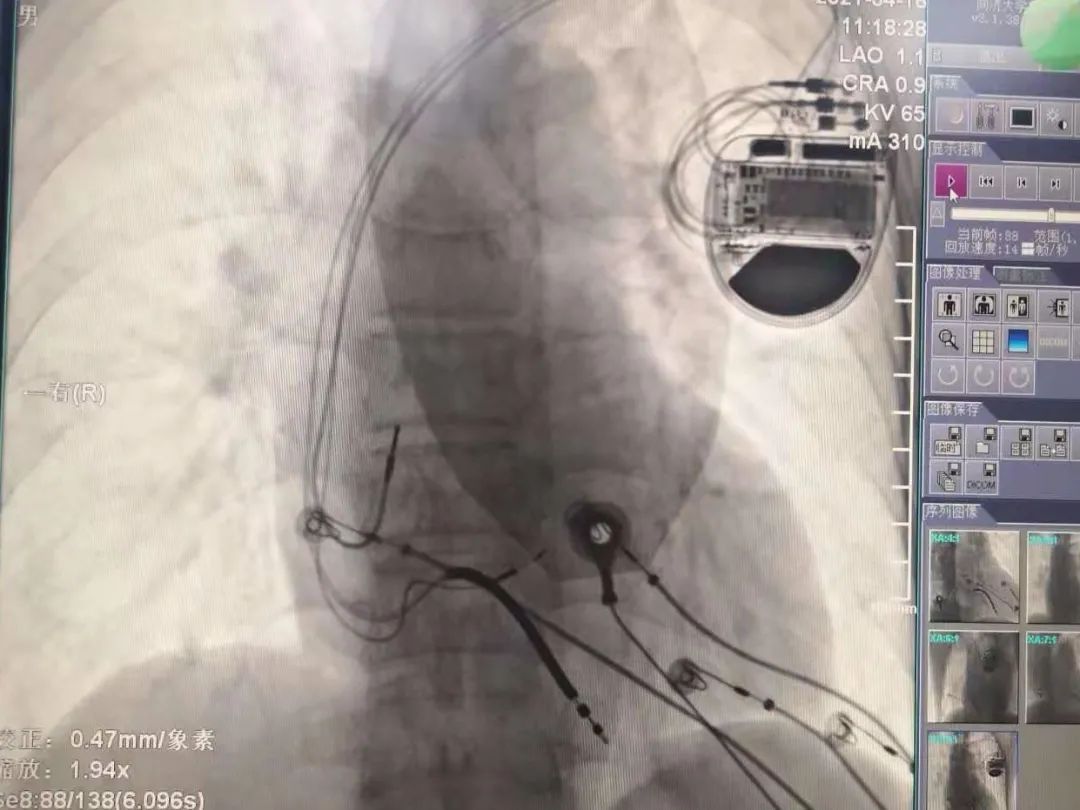

择日,孙冰主任医师和毛玉副主任医师所在的起搏团队为先生进行了起搏器植入手术。张先生植入的起搏器为三腔起搏器,共有三根导线经血管到达心脏,分别位于右心房、右心室和左束支。右心房、右心室得电极保证了心房心室收缩的同步性,并具有防治室速室颤的功能。而左束支电极可以纠正左束支传导阻滞,实现左室内部的收缩同步,改善心功能。经过精细定位和检测,左束支电极植入成功,起搏后可以看到张先生心电图的QRS波迅速变窄,标志左室收缩同步性的达峰时间和胸前导联QRS波移行也非常理想。手术很成功。术后心电图已经看不到原来宽宽的QRS波了,几乎与正常心电图完全一样。这意味着心脏电传导得到了改善,张先生的脸上也露出了笑容。

术前;术后